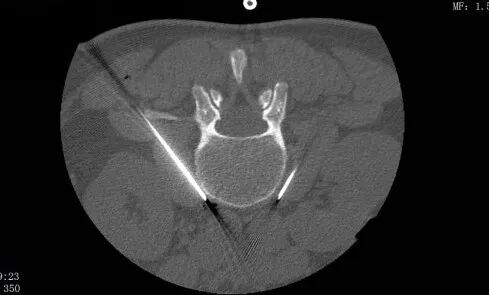

經(jīng)惠州三院疼痛科醫(yī)療團隊討論,最終決定采用目前先進的“腰交感神經(jīng)射頻調(diào)制術(shù)”為患者的“寒腿”送溫暖。在做好充分的術(shù)前準(zhǔn)備后,醫(yī)生順利為患者施行了CT引導(dǎo)下腰3交感神經(jīng)射頻調(diào)制術(shù)。

王鑫醫(yī)生說,腰交感神經(jīng)對下肢血管有支配作用,其中腰3神經(jīng)節(jié)具有重要作用。通過CT精準(zhǔn)引導(dǎo)射頻調(diào)節(jié)腰3交感神經(jīng)結(jié),使交感神經(jīng)興奮性降低,不僅能增加腰部動靜脈的血流量,緩解神經(jīng)根缺血導(dǎo)致的疼痛和麻木感,還能擴張其支配的下肢血管,使腿部整體的血液循環(huán)得到改善。